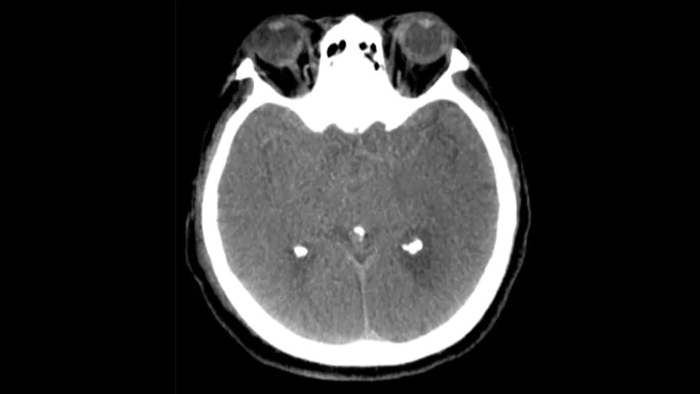

O SmartCT para Tecidos Moles gera uma visualização de tecidos moles semelhante à de uma tomografia computadorizada e facilita de três maneiras o diagnóstico de AVC: uma varredura sem contraste ajuda a detectar as primeiras alterações isquêmicas; uma varredura de fase inicial ajuda a identificar a oclusão proximal; e uma varredura aprimorada de fase avançada com contraste facilita a detecção dos fluxos sanguíneos colaterais.

Use as imagens do SmartCT para Tecidos Moles (semelhantes a TC) do pacote Neurovascular para verificar o sucesso do tratamento e sangramentos.